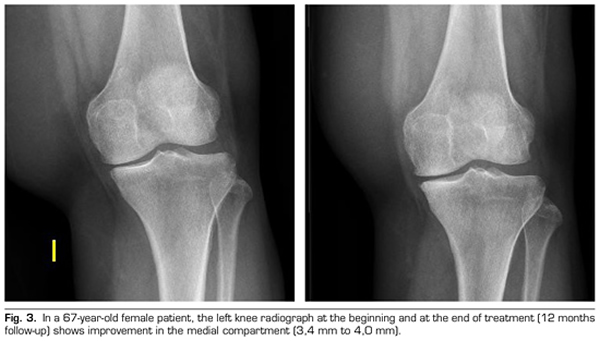

Figure 3

Radiological variables: In 53 patients analyzed radiologically (according to standardized protocol) at one year of follow-up after ozone treatment, the internal compartment increased significantly from 4.12 ± 1.41 mm to 4.4 ± 1.35 mm (p = 0.0008) and the external compartment increased from 6 ± 1.37 to 6.16 ± 1.4 mm (p = 0.0753).